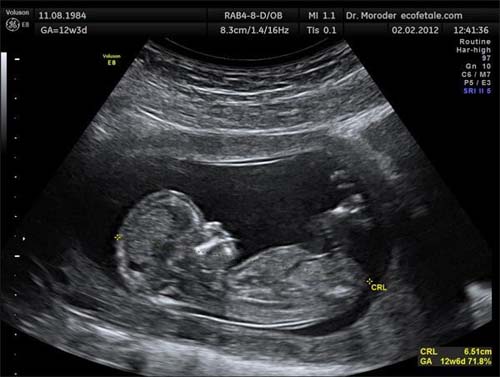

Đồng thời ở giai đoạn này phần đầu và thân của bé đã trở nên tương đối cân bằng hơn, mẹ có thể nhìn rõ được sự liên kết giữa đầu cũng như cổ của bé qua hình ảnh siêu âm.

Hình ảnh thai nhi 13 tuần tuổi lúc này rất rõ rệt, bác sỹ có thể soi được biểu cảm khuôn mặt bé, hành động và cử chỉ của bé. Thậm chí chỉ vào cuối tuần thai thứ 13 là cánh tay của bé sẽ có chiều dài cân đối với thân hình. Trên cơ thể con cũng sẽ mọc thêm một lớp lông tơ siêu mịn, các tế bào tóc cũng đang bắt đầu hình thành.

Thực tế khi bước vào tuần thai nhi thứ 13 tuần bộ phận sinh dục của bé đã phát triển và hiển thị rõ ra bên ngoài. Chỉ cần mẹ đi siêu âm là đã có thể xác định khá chính xác được giới tính của thai nhi, mẹ sẽ biết được em bé là trai hay gái đến khoảng 90%.

Thai 13 tuần đã có thể xác định giới tính qua siêu âm.

Tuy nhiên vẫn còn xác xuất nhỏ không chính xác bởi vì ở tuần này bộ phận sinh dục thai nhi 13 tuần chưa được rõ ràng bởi còn đang phát triển. Thêm vào đó một số thiết bị máy móc kém chất lượng cũng sẽ dễ dẫn tới chẩn đoán sau. Nhiều trường hợp bé còn nằm co chân hoặc nằm quay mặt vào trong hay dây rốn buông che mất nên khó xác định được.

Chính vì thế để nhận biết rõ hơn và chính xác giới tính của bé hơn đó là vào khoảng tuần 20-22, đây là lúc hầu hết các mẹ có thể biết chính xác được giới tính con yêu bởi lúc này nước ối nhiều hơn và bộ phận sinh dục cũng hoàn thiện hơn, dễ chẩn đoán hơn.